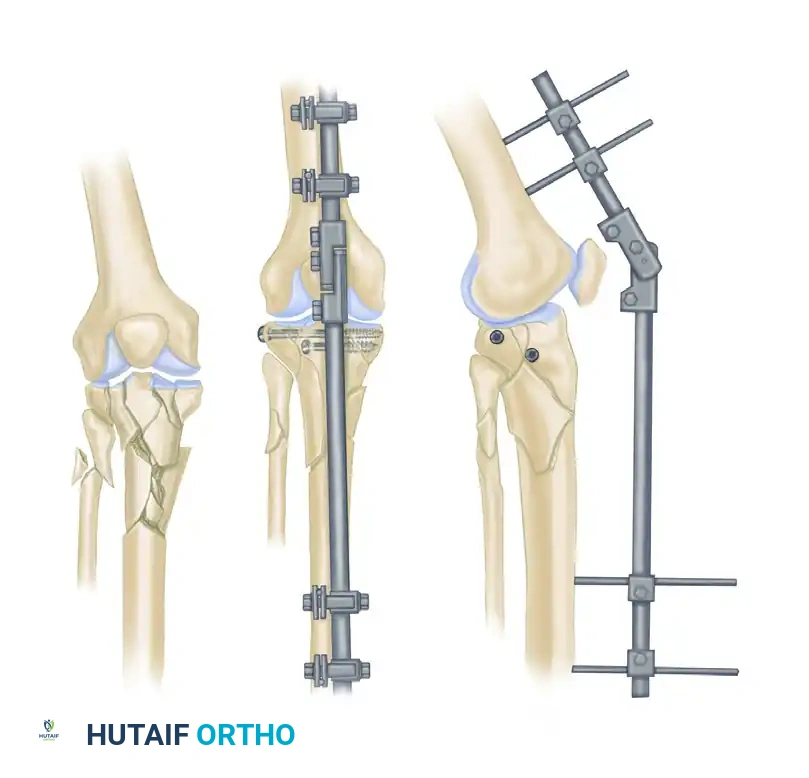

- Pelvic Ring Disruptions: For acute volume reduction and stabilization of hemodynamically unstable pelvic fractures (e.g., open-book injuries).

- Ligamentotaxis: Utilizing the fixator to apply traction across a joint, utilizing the intact capsuloligamentous structures to reduce intra-articular fracture fragments (commonly used in distal radius and tibial pilon fractures).

- Floating Knee Injuries: Ipsilateral femoral and tibial fractures where rapid stabilization is required to permit early joint mobilization.

- Adjustability: Postoperative adjustments to alignment can be made in the clinic without returning to the operating room.

- Joint Stiffness: If the frame spans a joint (e.g., ankle or knee), prolonged immobilization can lead to severe capsular fibrosis.

The Femur

- Distal Femur: The safe zone is strictly lateral or anterior. Medial pins risk injury to the superficial femoral artery and vein in the adductor canal.

- Proximal Femur: Pins are typically placed laterally, aiming toward the lesser trochanter, avoiding the femoral neurovascular bundle anteriorly and the sciatic nerve posteriorly.